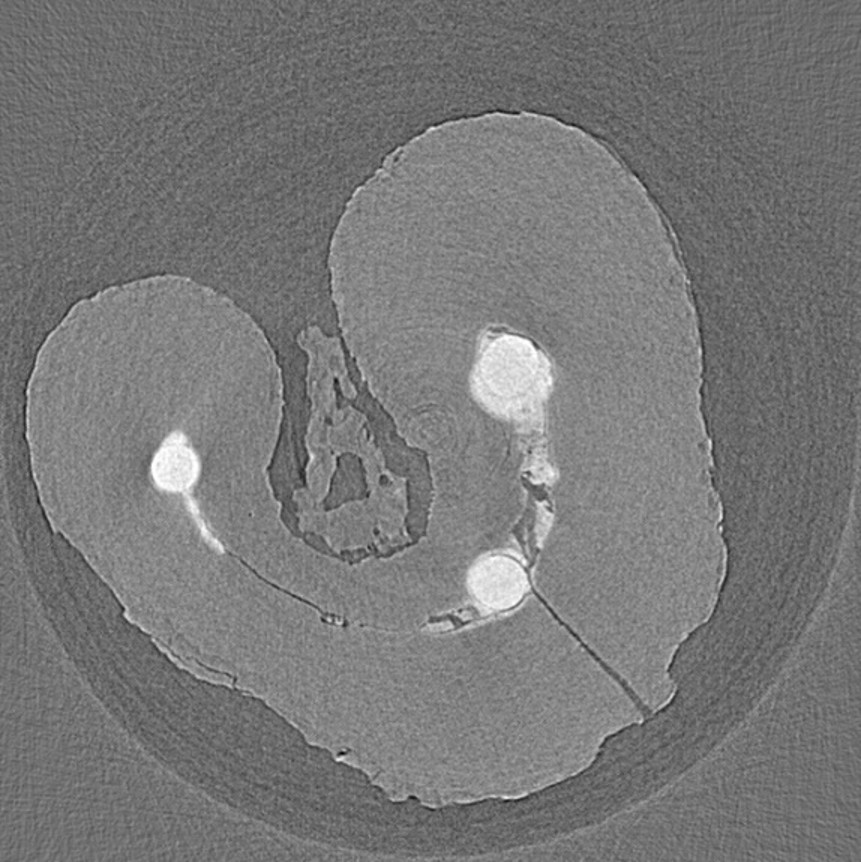

expected_medical_image

양자 CT 이미지 예측 결과

양자 알고리즘은 기존 알고리즘 대비 높은 수렴성을 가지고 있어, 제한된 데이터에서도 뛰어난 복원력을 발휘하며, 이를 통해 진단 이미지의 선명도와 정확도를 획기적으로 향상시킬 수 있습니다. 또한, 양자 알고리즘의 계산 효율성과 높은 복원력 덕분에 기존 CT 검사 대비 적은 방사선 노출량만으로도 고해상도 영상을 얻을 수 있어 환자의 안전성을 높이고, 검사 효율성을 향상시키는 데 기여할 것으로 기대됩니다.

기존 재건 알고리즘인 SART와 FBP는 sinogram 데이터 손실이나 제한된 투영 각도에서 성능이 저하되어 흐릿하고 정확도가 낮은 영상을 생성하지만 양자 알고리즘은 높은 정확도를 가지는 양자 CT 이미지를 재건합니다.